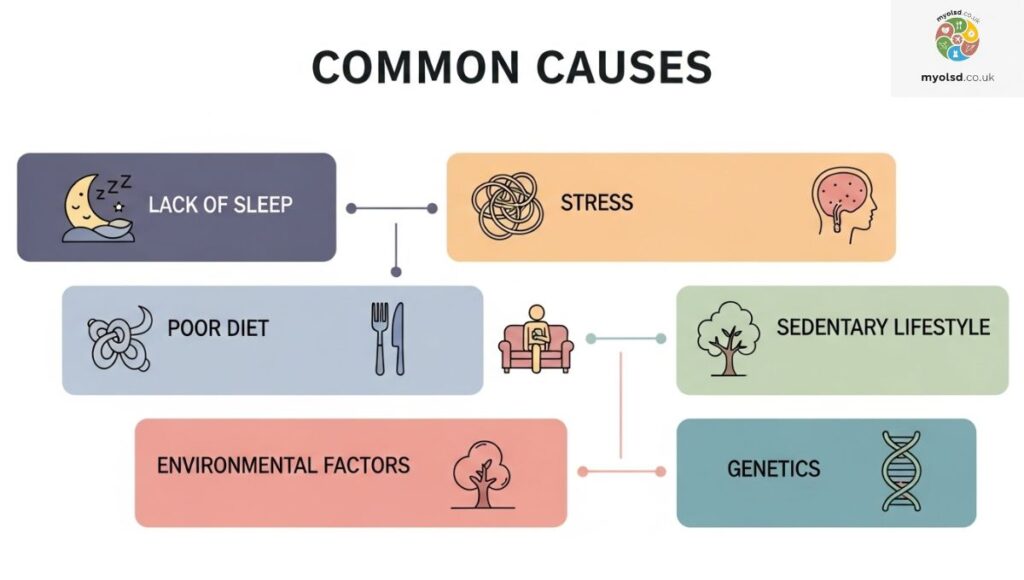

Common Causes

Morning ankle pain isn’t just a random annoyance. It’s usually your body’s way of signaling an underlying issue. Some of the most common culprits include:

- Arthritis – Chronic joint inflammation can make your ankles stiff and sore, especially after periods of rest.

- Tendinitis – Inflammation of the tendons, like the Achilles tendon, often feels worse when you first get up.

- Ankle Sprain – Even a mild sprain from a previous injury can leave lingering stiffness in the morning.

- Trip or Impact Injuries – Accidental missteps or small falls can cause micro-injuries that only show up when you move after rest.

- Overuse – Activities like running, standing all day, or wearing unsupportive shoes can strain your ankles overnight.

Recognizing which of these applies to you can help you target your treatment more effectively.